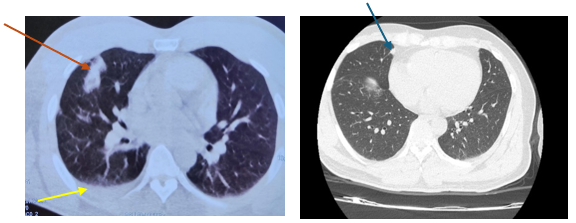

Đến 6 tháng sau bệnh nhân đi khám sức khoẻ được chụp cắt lớp vi tính lồng ngực cho kết quả:Vài nốt đặc thùy giữa và dưới phổi phải, nốt lớn kích thước 10x25mm, tràn dịch màng phổi phải => vào Trung tâm Y học hạt nhân và Ung bướu đánh giá và điều trị

Hình 1: Hình ảnh  cắt lớp vi tính lồng ngực: nốt tổn thương u phổi phải kích thước 10x25mm (mũi tên đỏ), dịch màng phổi phải (mũi tên vàng), tổn thương di căn phổi (mũi tên xanh).

Bệnh nhân được chụp PET/CT tại Bệnh viện Vinmec cho kết quả: Các nốt đặc rải rác thùy giữa và dưới phổi phải, các nốt lớn tăng chuyển hoá FDG (suvmax 3,6), ít dịch màng phổi dày 9mm, nhiều nốt rải rác màng phổi thành ngực, hạch nhóm 2R,4R/7 rốn phổi phải, hạch lớn KT 17x10mm.

Hình 3: Hình ảnh chụp PET/CT các nốt tổn thương u tại phổi phải (mũi tên đỏ), nốt di căn màng phổi phải (mũi tên vàng)